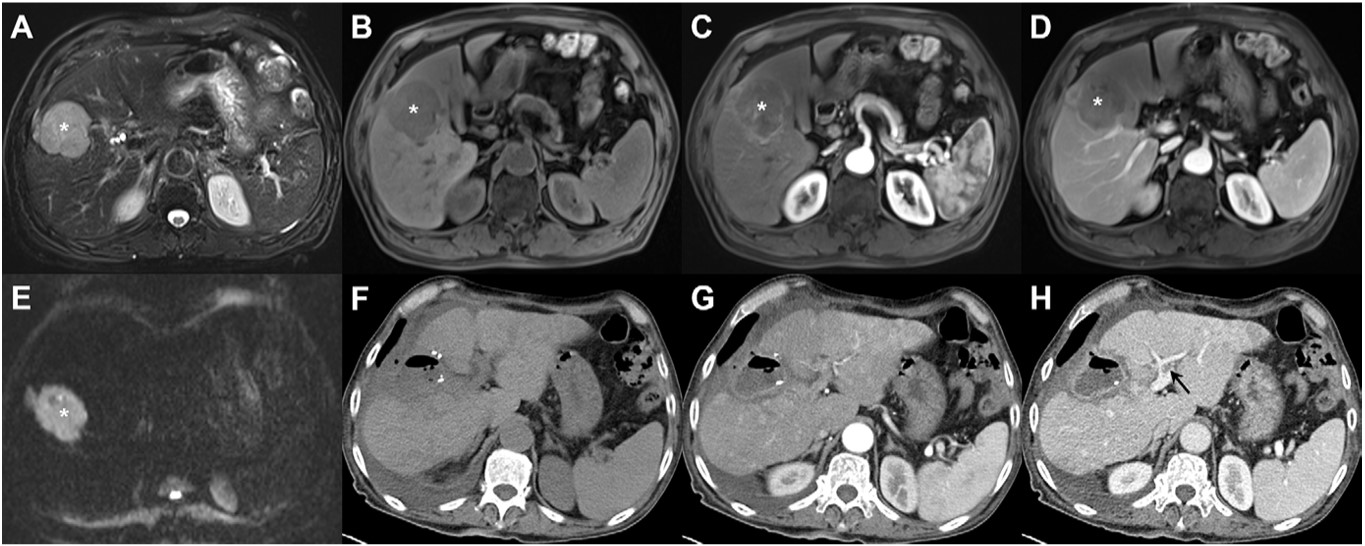

They tested the three models in a study of 120 patients diagnosed with liver cancer between June 2005 and March 2018 and who had a transplant, resection, or thermal ablation. All patients underwent an MRI exam before treatment and were followed up with MRI after treatment. Of the study participants, 36.7% experienced tumor recurrence during follow-up.

Using area under the receiver operating curve (AUC) to assess each model's performance, Iseke's group found that the MRI data machine-learning model improved clinicians' ability to predict liver cancer recurrence after treatment better than the laboratory/clinical features model did. The group also found that, overall, the combined model did not outperform the imaging model (despite a slightly higher AUC in the combined model compared to the MRI model in year six).